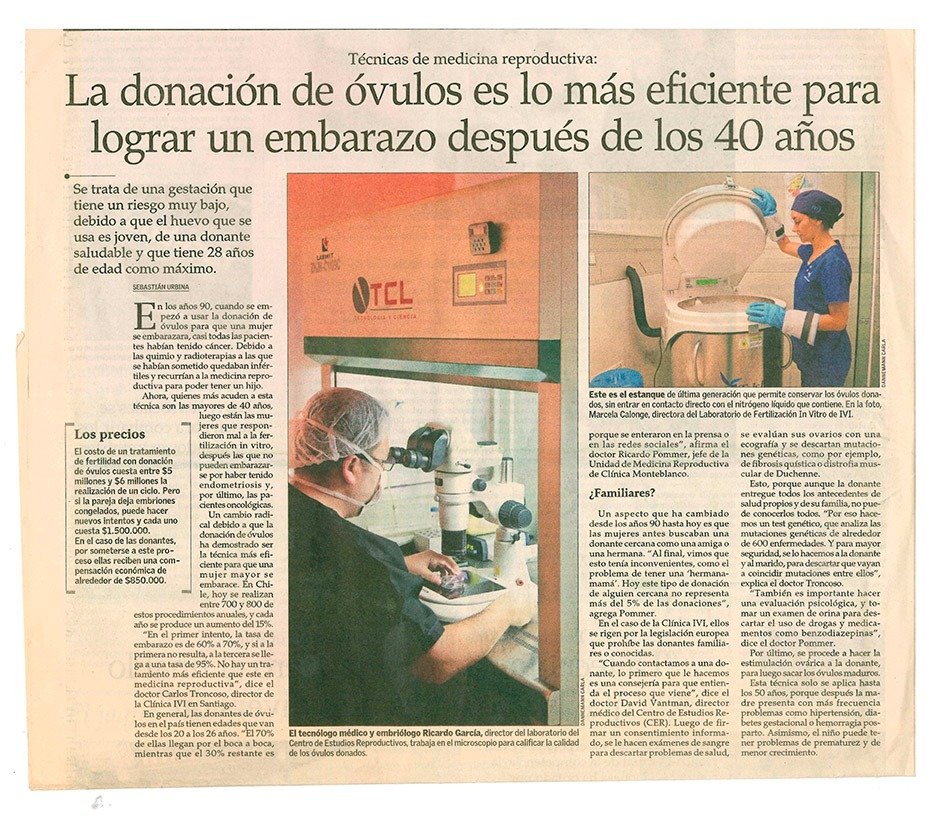

Envejecimiento y reducción de óvulos son algunas de las razones que pueden producir infertilidad. Hoy, la tecnología ofrece una nueva oportunidad para experimentar la maternidad, se trata de la ovodonación. Tratamiento que permite la fecundación con óvulos donados y transferidos al útero de la madre, una tendencia que ha crecido en el país, la cual ha permitido más de 3 mil nacimientos.